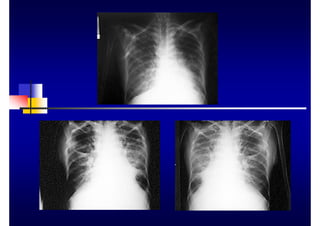

RADIOLOGÍA

„ Utilidad

„ diagnóstico

„ pronóstico

„ tratamiento

„ Técnicas

„ periapicales cono largo

„ panorámicas

„ aletas de mordida

„ serie radiográfica

„ Limitaciones

„ bolsas periodontales

„ destrucción ósea V y L

„ tejidos blandos

„ gingivorragia

„ movilidad dentaria

„